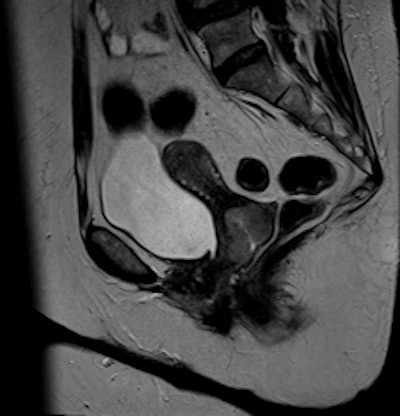

The uterine zonal anatomy and cervix are more sharply delineated on the BLADE image (right); however, SNR and CNR are higher on the conventional T2-weighted image (left). All images courtesy of Dr. Bianka Freiwald-Chilla.Previous studies have focused primarily on visual and qualitative assessment of images, so Froehlich and colleagues prospectively compared overall image quality, contrast, and diagnostic information of the recently implemented T2-weighted BLADE TSE sequence with the conventional Cartesian T2-weighted TSE sequence in female pelvic organs.

They found BLADE significantly (p < 0.0001) reduced motion and ghosting artifacts and showed improved conspicuity, but overall image quality did not differ significantly in the 47 patients who underwent sagittal BLADE and conventional TSE at 1.5-tesla after glucagon administration. In the majority of cases (53.2% versus 59.6%), radiologists preferred conventional TSE due to better image contrast and visibility of free pelvic fluid. Signal-to-noise ratio (SNR) and contrast-to-noise ratio (CNR) were significantly higher on conventional TSE.

Cervical carcinoma: The uterine zonal anatomy and bladder wall as well as the bowel loops are more sharply delineated on the BLADE image (right); however, SNR and CNR are higher on the conventional T2-weighted image (left)."Indeed, conventional T2-weighted TSE provided a significantly better visibility of free pelvic fluid or cystic structures (i.e., a relatively higher effective T2 weighting) in numerous cases," the researchers noted.